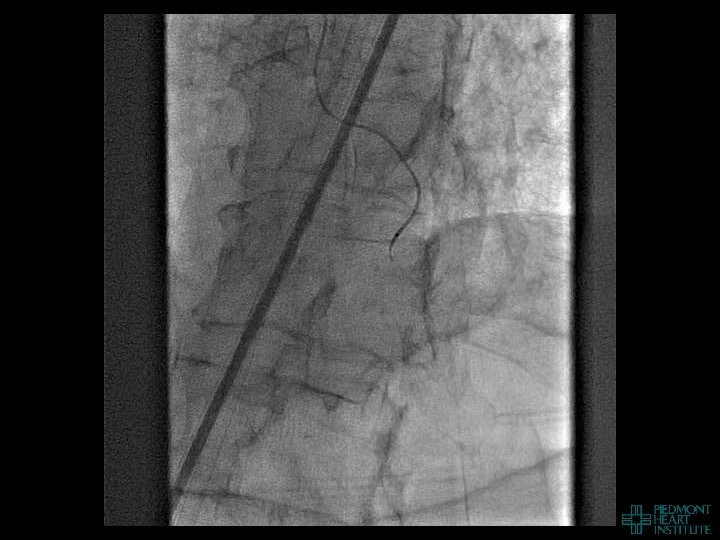

Case Example 4